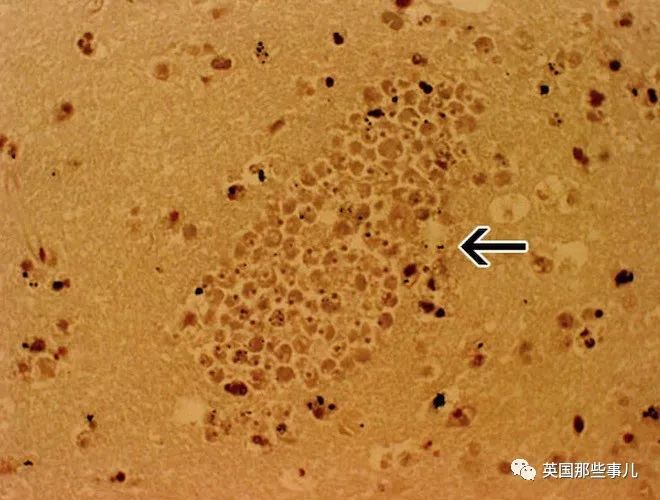

一大团食脑虫包围毛细血管